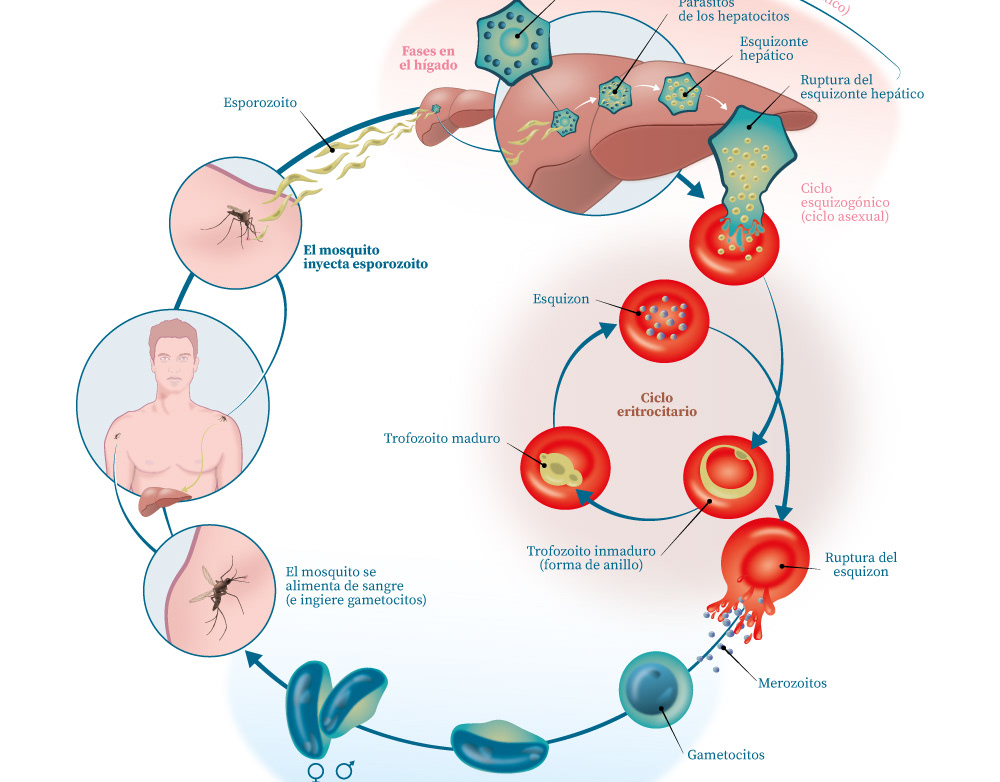

Infografía / Infectología

Infografía / Infectología